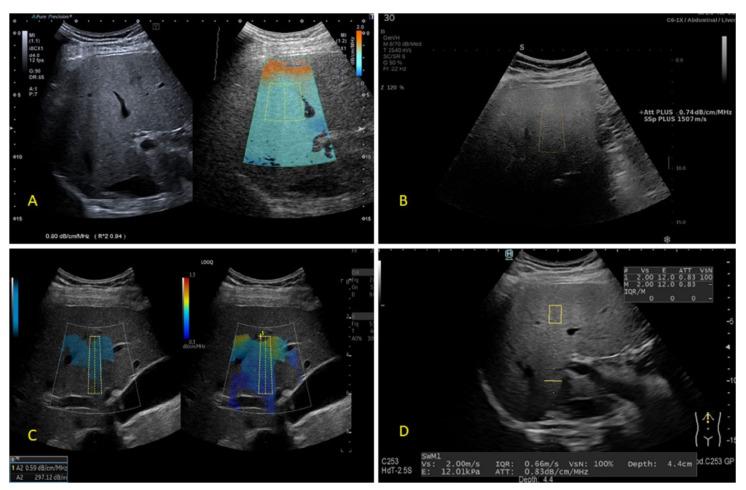

The prevalence of the non-alcoholic fatty liver disease has reached major proportions, being estimated to affect one-quarter of the global population. The reference techniques, which include liver biopsy and the magnetic resonance imaging proton density fat fraction, have objective practical and financial limitations to their routine use in the detection and quantification of liver steatosis. Therefore, there has been a rising necessity for the development of new inexpensive, widely applicable and reliable non-invasive diagnostic tools. The controlled attenuation parameter has been considered the point-of-care technique for the assessment of liver steatosis for a long period of time. Recently, many ultrasound (US) system manufacturers have developed proprietary software solutions for the quantification of liver steatosis. Some of these methods have already been extensively tested with very good performance results reported, while others are still under evaluation. This manuscript reviews the currently available US-based methods for diagnosing and grading liver steatosis, including their classification and performance results, with an appraisal of the importance of this armamentarium in daily clinical practice.

非酒精性脂肪性肝病的患病率已达到相当大的比例,据估计影响全球四分之一的人口。包括肝活检和磁共振成像质子密度脂肪分数在内的参考技术在其用于肝脂肪变性检测和定量的常规应用中存在客观的实际和经济限制。因此,开发新的廉价、广泛适用且可靠的非侵入性诊断工具的需求日益增加。受控衰减参数长期以来一直被视为评估肝脂肪变性的即时检测技术。最近,许多超声(US)系统制造商已经开发出用于肝脂肪变性定量的专有软件解决方案。其中一些方法已经经过广泛测试,报告的性能结果非常好,而其他方法仍在评估中。本文综述了目前可用的基于超声的肝脂肪变性诊断和分级方法,包括它们的分类和性能结果,并评估了这套方法在日常临床实践中的重要性。